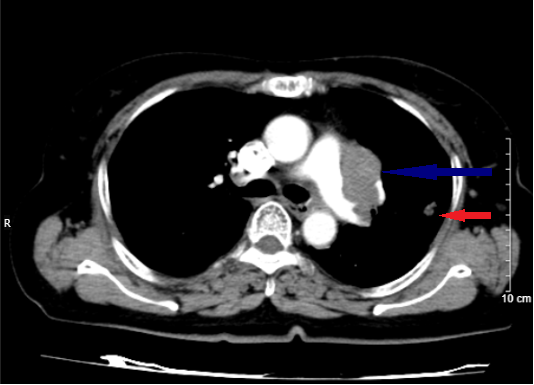

Hình 1: Hình ảnh cắt lớp vi tính lồng ngực lúc mới chẩn đoán (mũi tên xanh: khối ở trung thất giữa; mũi tên đỏ: nốt đặc ở phổi cùng bên).

Hình 2: Hình ảnh trước điều trị (bên trái): Hình ảnh khối u và tổn thương di căn phổi cùng bên (mũi tên đỏ). Hình ảnh sau điều trị (bên phải): không còn khối u sau 3 chu kì điều trị

Hình 3: Hình bên trái (trước điều trị): Hình ảnh khối u (mũi tên vàng). Hình bên phải (sau điều trị): không còn tổn thương di căn phổi cùng bên sau 3 chu kì điều trị